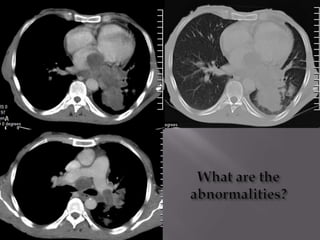

WHAT ARE THE 3 ABNORALITIES?

1). DIFFUSE HYPER DENSITY IN THE LIVER.

(2ry haemachromatosis/transfusional siderosis).

2).MULTIPLE GALLSTONES.

3). SPLENECTOMY.